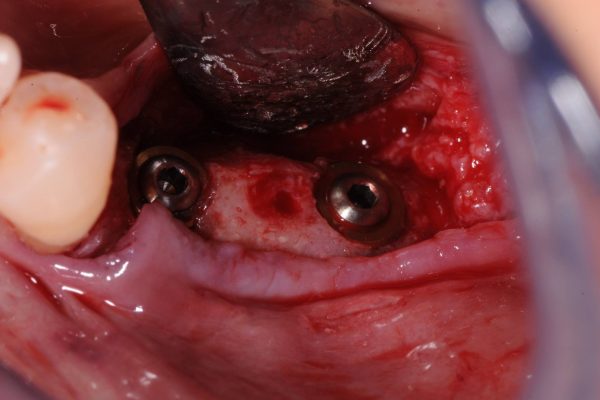

Importante perdita ossea Verticale ed orizzontale provocata dalla perdita di Impianti posizionati a causa della MANCANZA di una attenta diagnosi, piano di trattamento e capacità operativa, che avrebbero mostrato l’impossibilita di posizionare gli Impianti senza ripristinare lo spessore osseo adeguato …